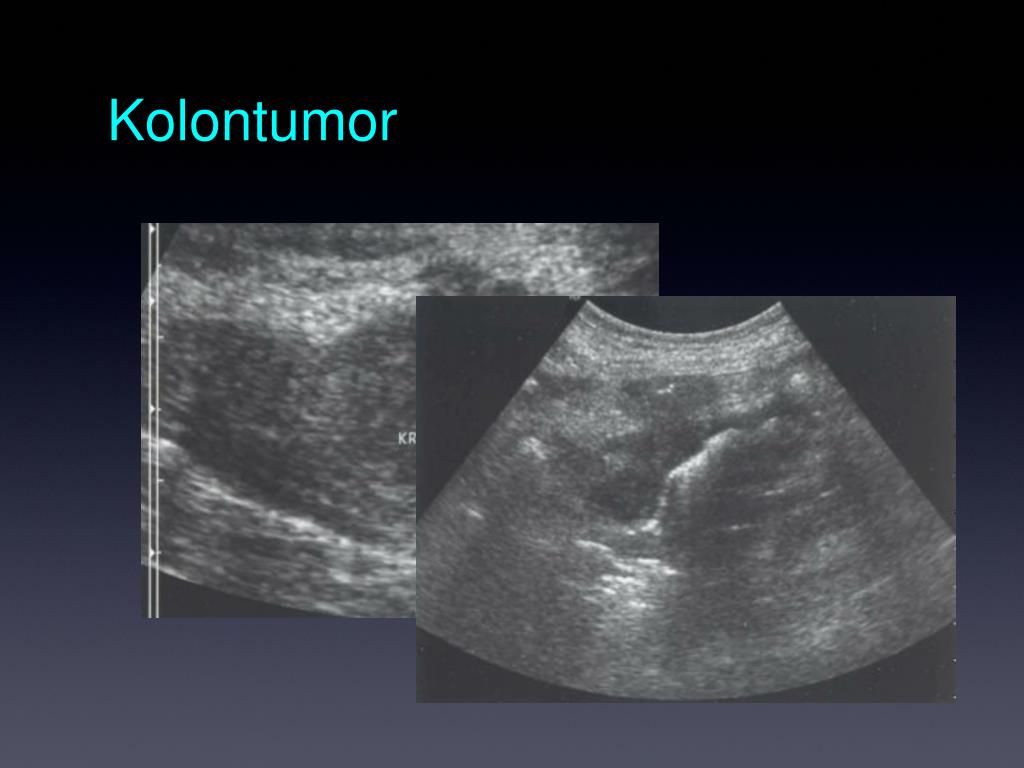

38. Kolontumor